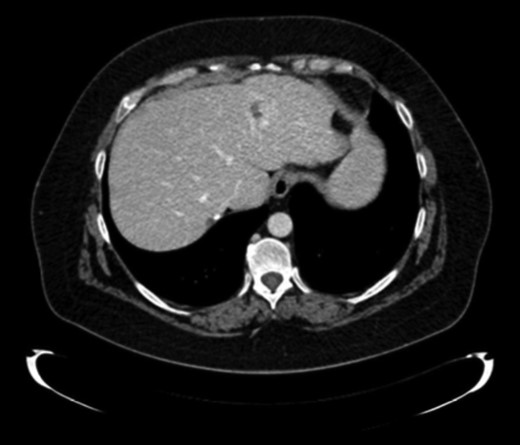

Finally, 12 months after this second liver surgery, a new hepatic lesion in left hepatic lobe of 3 cm was identified (Fig. 4). Systemic treatment was re-initiated with Cisplatin (75 mg/m2) and Cetuximab for 2 months. After that, left hepatectomy was performed with tumor-free surgical margins without subsequent complications. Surgical specimen revealed undifferentiated tumor.